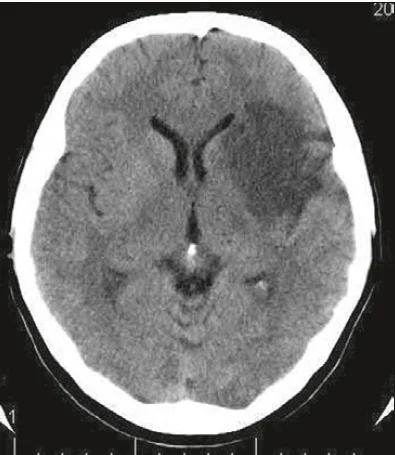

На рентгенограмі патологічних вогнищ не виявлено. При комп’ютерній томографії ГМ виявлене велике вогнище зниженої щільності у правій півкулі, відзначалася компресія правого бокового шлуночка (рисунок). Під час проведення правої каротидної ангіографії: закупорювання основного стовбура середньої мозкової артерії, контрастування кіркових гілок середньої мозкової артерії з заповненням із передньої та задньої мозкових артерій.

Рисунок. Комп’ютерна томографія ГМ пацієнта